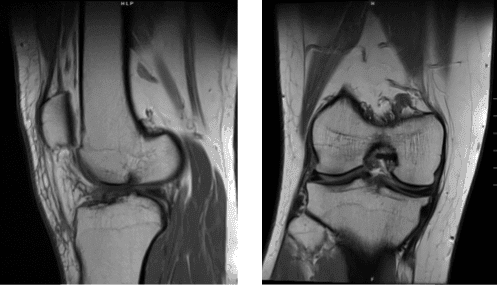

Se revisaron y debatieron las resonancias magnéticas; la elevación lineal de la señal se identifica en la parte posterior del menisco medial en la secuencia coronal #12 y en la secuencia sagital #26 asociada a desgarros intrasustanciales. No se aprecia el desgarro dentro del menisco lateral.

Se observa la preservación de la altura del espacio articular tanto en los compartimentos femorotibiales medial como lateral. Se observa una intensidad intermedia de señal asociada con el ligamento cruzado anterior, lo que sugiere esguince.

No hay evidencia de discontinuidad o retracción del ligamento cruzado posterior que indique desgarro. No hay evidencia de desgarro del ligamento colateral medial. No hay evidencia de desgarro del ligamento colateral lateral.

No hay evidencia de desgarro del tendón del cuádriceps. No hay evidencia de desgarro del tendón rotuliano. No hay evidencia de desgarro del retináculo patuliano medial o lateral. Fluido peritendino poplíteo asociado a tenosinovitis.

El líquido peritendino semimembranoso y semitendinoso también está asociado con tenosinovitis. No hay evidencia de cambios en la señal asociados con la banda iliotibial. No hay evidencia de cambios degenerativos en la articulación tibiofemoral proximal.

Se observa un leve derrame articular tanto en componentes suprapatelares como infrapatelares. No hay evidencia de quiste de Baker posterior al cóndilo femoral medial. No hay evidencia de condromalacia en la rótula posterior.

La distancia entre el tubérculo tibial y la ranura trocleare mide aproximadamente 5 mm dentro de los límites normales. Se observa edema de tejido blando anterior en trazas. No hay evidencia de cambio en la señal de médula ósea que indique fractura, necrosis avascular, osteomielitis o proceso de reemplazo de médula ósea.

Impresión: Desgarro intrasustancial del cuerno posterior del menisco medial. Esguince del ligamento cruzado anterior. Tenosinovitis de poplíteo, semimembranoso y semitendinoso y derrame leve. Lo que significa que los resultados de la resonancia mostraron desgarro del menisco medial y desgarro del LCA.

Escaneo por resonancia magnética de la rodilla derecha